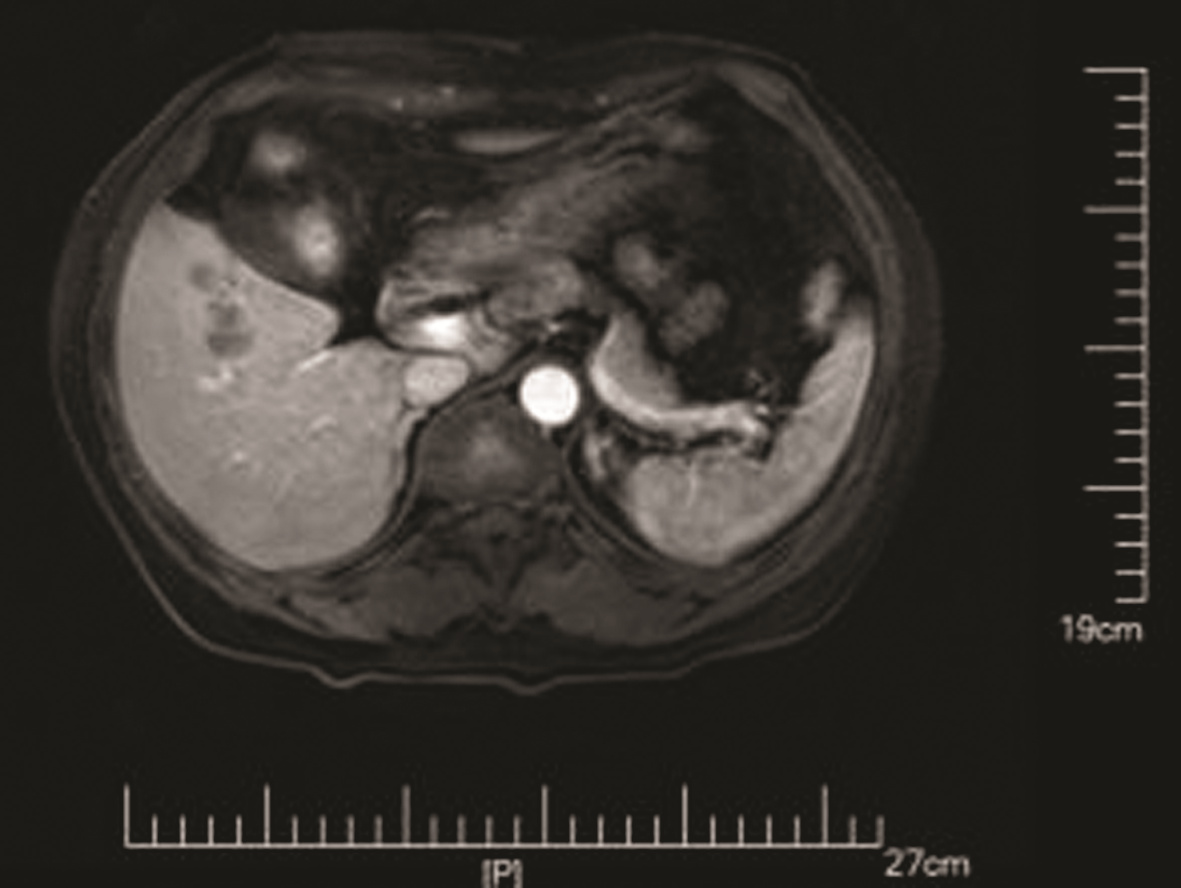

IgG4-related retroperitoneal fibrosis: A case report

Zhaoxia LI, Yang LIU, Nan LI, Zhuhui JI, Guijie XIN

2022, 38(5): 1126-1128. DOI: 10.3969/j.issn.1001-5256.2022.05.030

Abstract(758) HTML (364) PDF (2161KB)(55)

Abstract: